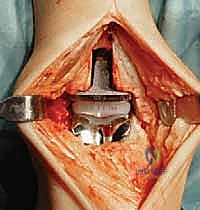

4. تركيب المفصل الصناعي (Implantation)

يتكون مفصل الكاحل الصناعي الحديث عادة من ثلاثة أجزاء:

* قطعة معدنية علوية: تُثبت في عظمة الظنبوب (الساق).

* قطعة معدنية سفلية: تُثبت في عظمة الكاحل.

* قطعة بلاستيكية (بولي إيثيلين عالي الكثافة): توضع بين القطعتين المعدنيتين لتنزلق بسلاسة وتمتص الصدمات، محاكيةً وظيفة الغضروف الطبيعي.

يتم تثبيت هذه الأجزاء بإحكام (إما عن طريق الضغط المباشر لتشجيع نمو العظم حولها، أو باستخدام أسمنت طبي خاص).

5. إغلاق الجرح والجبيرة

بعد التأكد من استقرار المفصل الجديد ومدى حركته الممتاز، يقوم د. هطيف بإغلاق الشق الجراحي باستخدام خيوط تجميلية دقيقة لتقليل الندبات. يتم وضع الكاحل في جبيرة أو حذاء طبي خاص لحمايته خلال الأسابيع الأولى من التعافي.